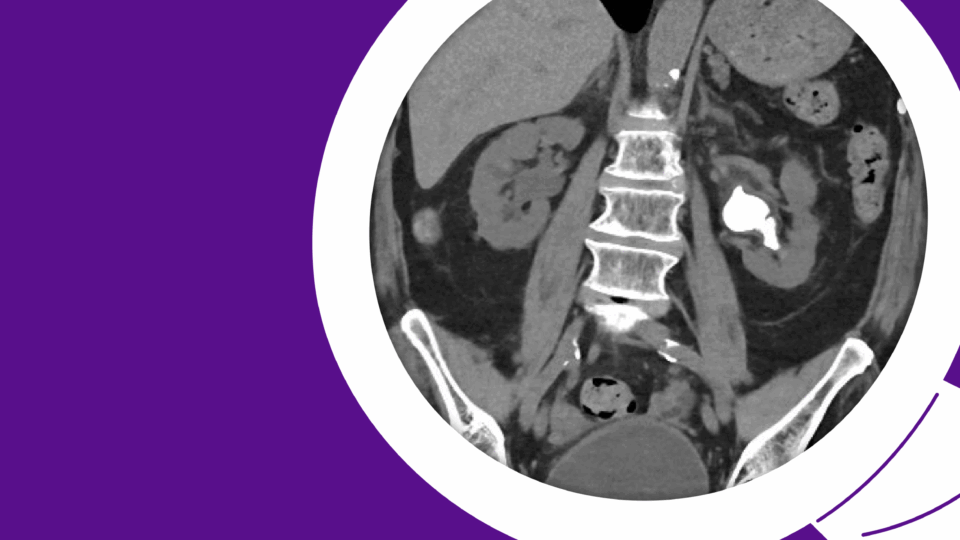

Before routine prostate-specific antigen (PSA) screening, prostate cancer was often diagnosed at an advanced stage, warranting radiographic staging prior to the initiation of treatment. However, since most new diagnoses today are clinically localized, the practice has become obsolete.

In their push for medical resource stewardship, the American Society of Clinical Oncology and the American Urological Association place significant emphasis on reducing the utilization of nuclear medicine bone scanning for early-stage prostate cancer.